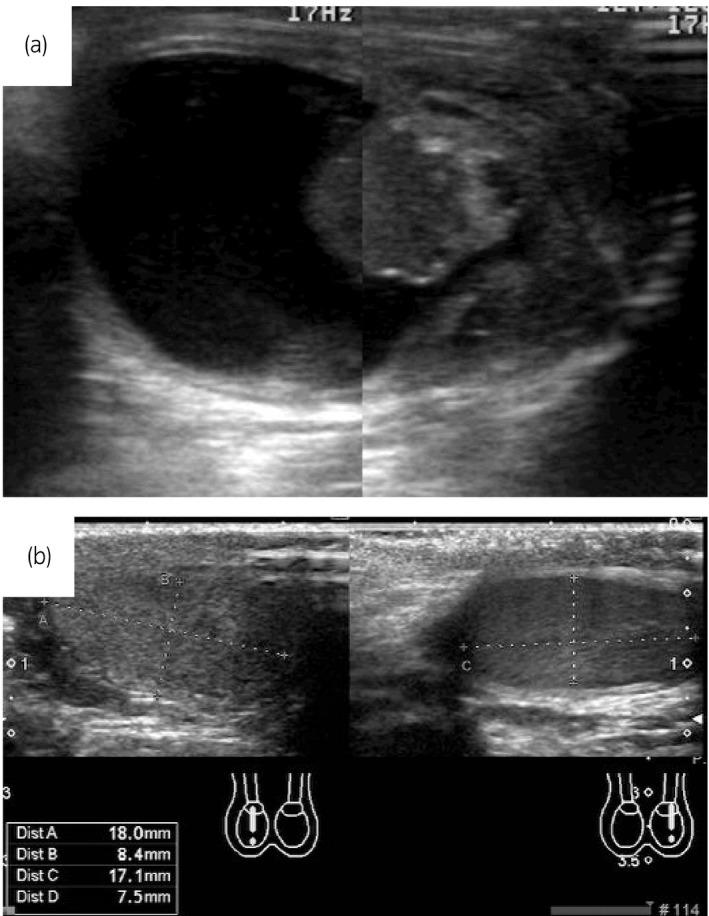

We treated 7 teratomas in 6 patients aged 12 years of younger. For 2 noncystic lesions, the spermatic cord was exposed via the transinguinal approach and clamped until the establishment of an intraoperative pathological diagnosis. The other 5 tumors in 4 infant patients were all preoperatively diagnosed with cystic teratoma, and we essentially exposed the testis directly via the scrotal approach and enucleated the tumor without clamping the cord. In every case, adequate amount of normal testicular tissue was preserved, without any local recurrence with 3-year minimum follow-up.

An unclamped enucleation of testicular tumor via the transscrotal approach, which is contraindicated in most testicular tumors, can be a treatment choice exclusively for preoperatively diagnosed mature cystic teratoma in infants.